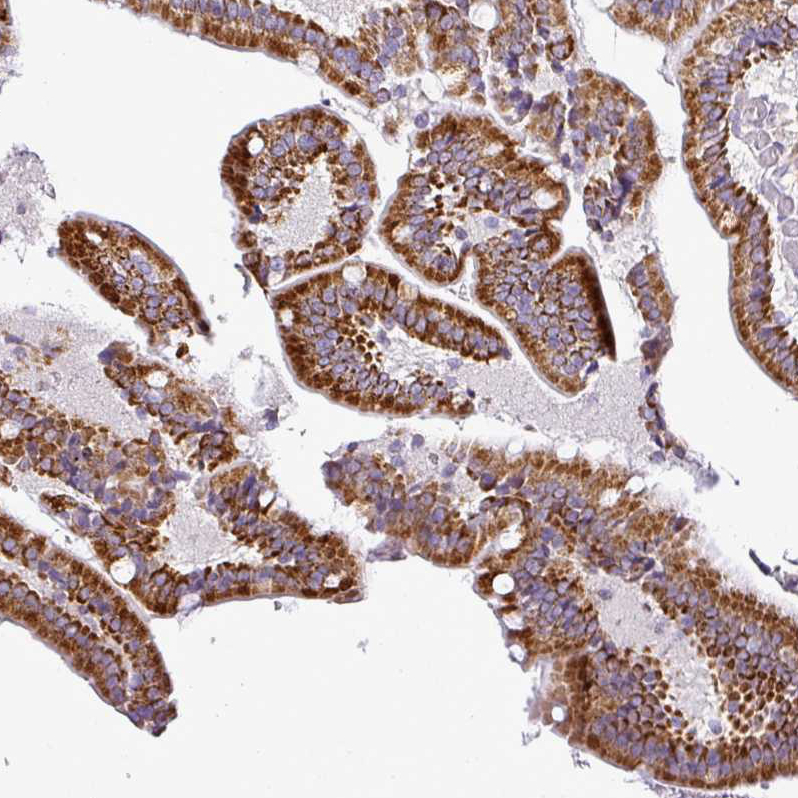

Immunohistochemical staining of human duodenum shows strong granular cytoplasmic positivity in glandular cells.